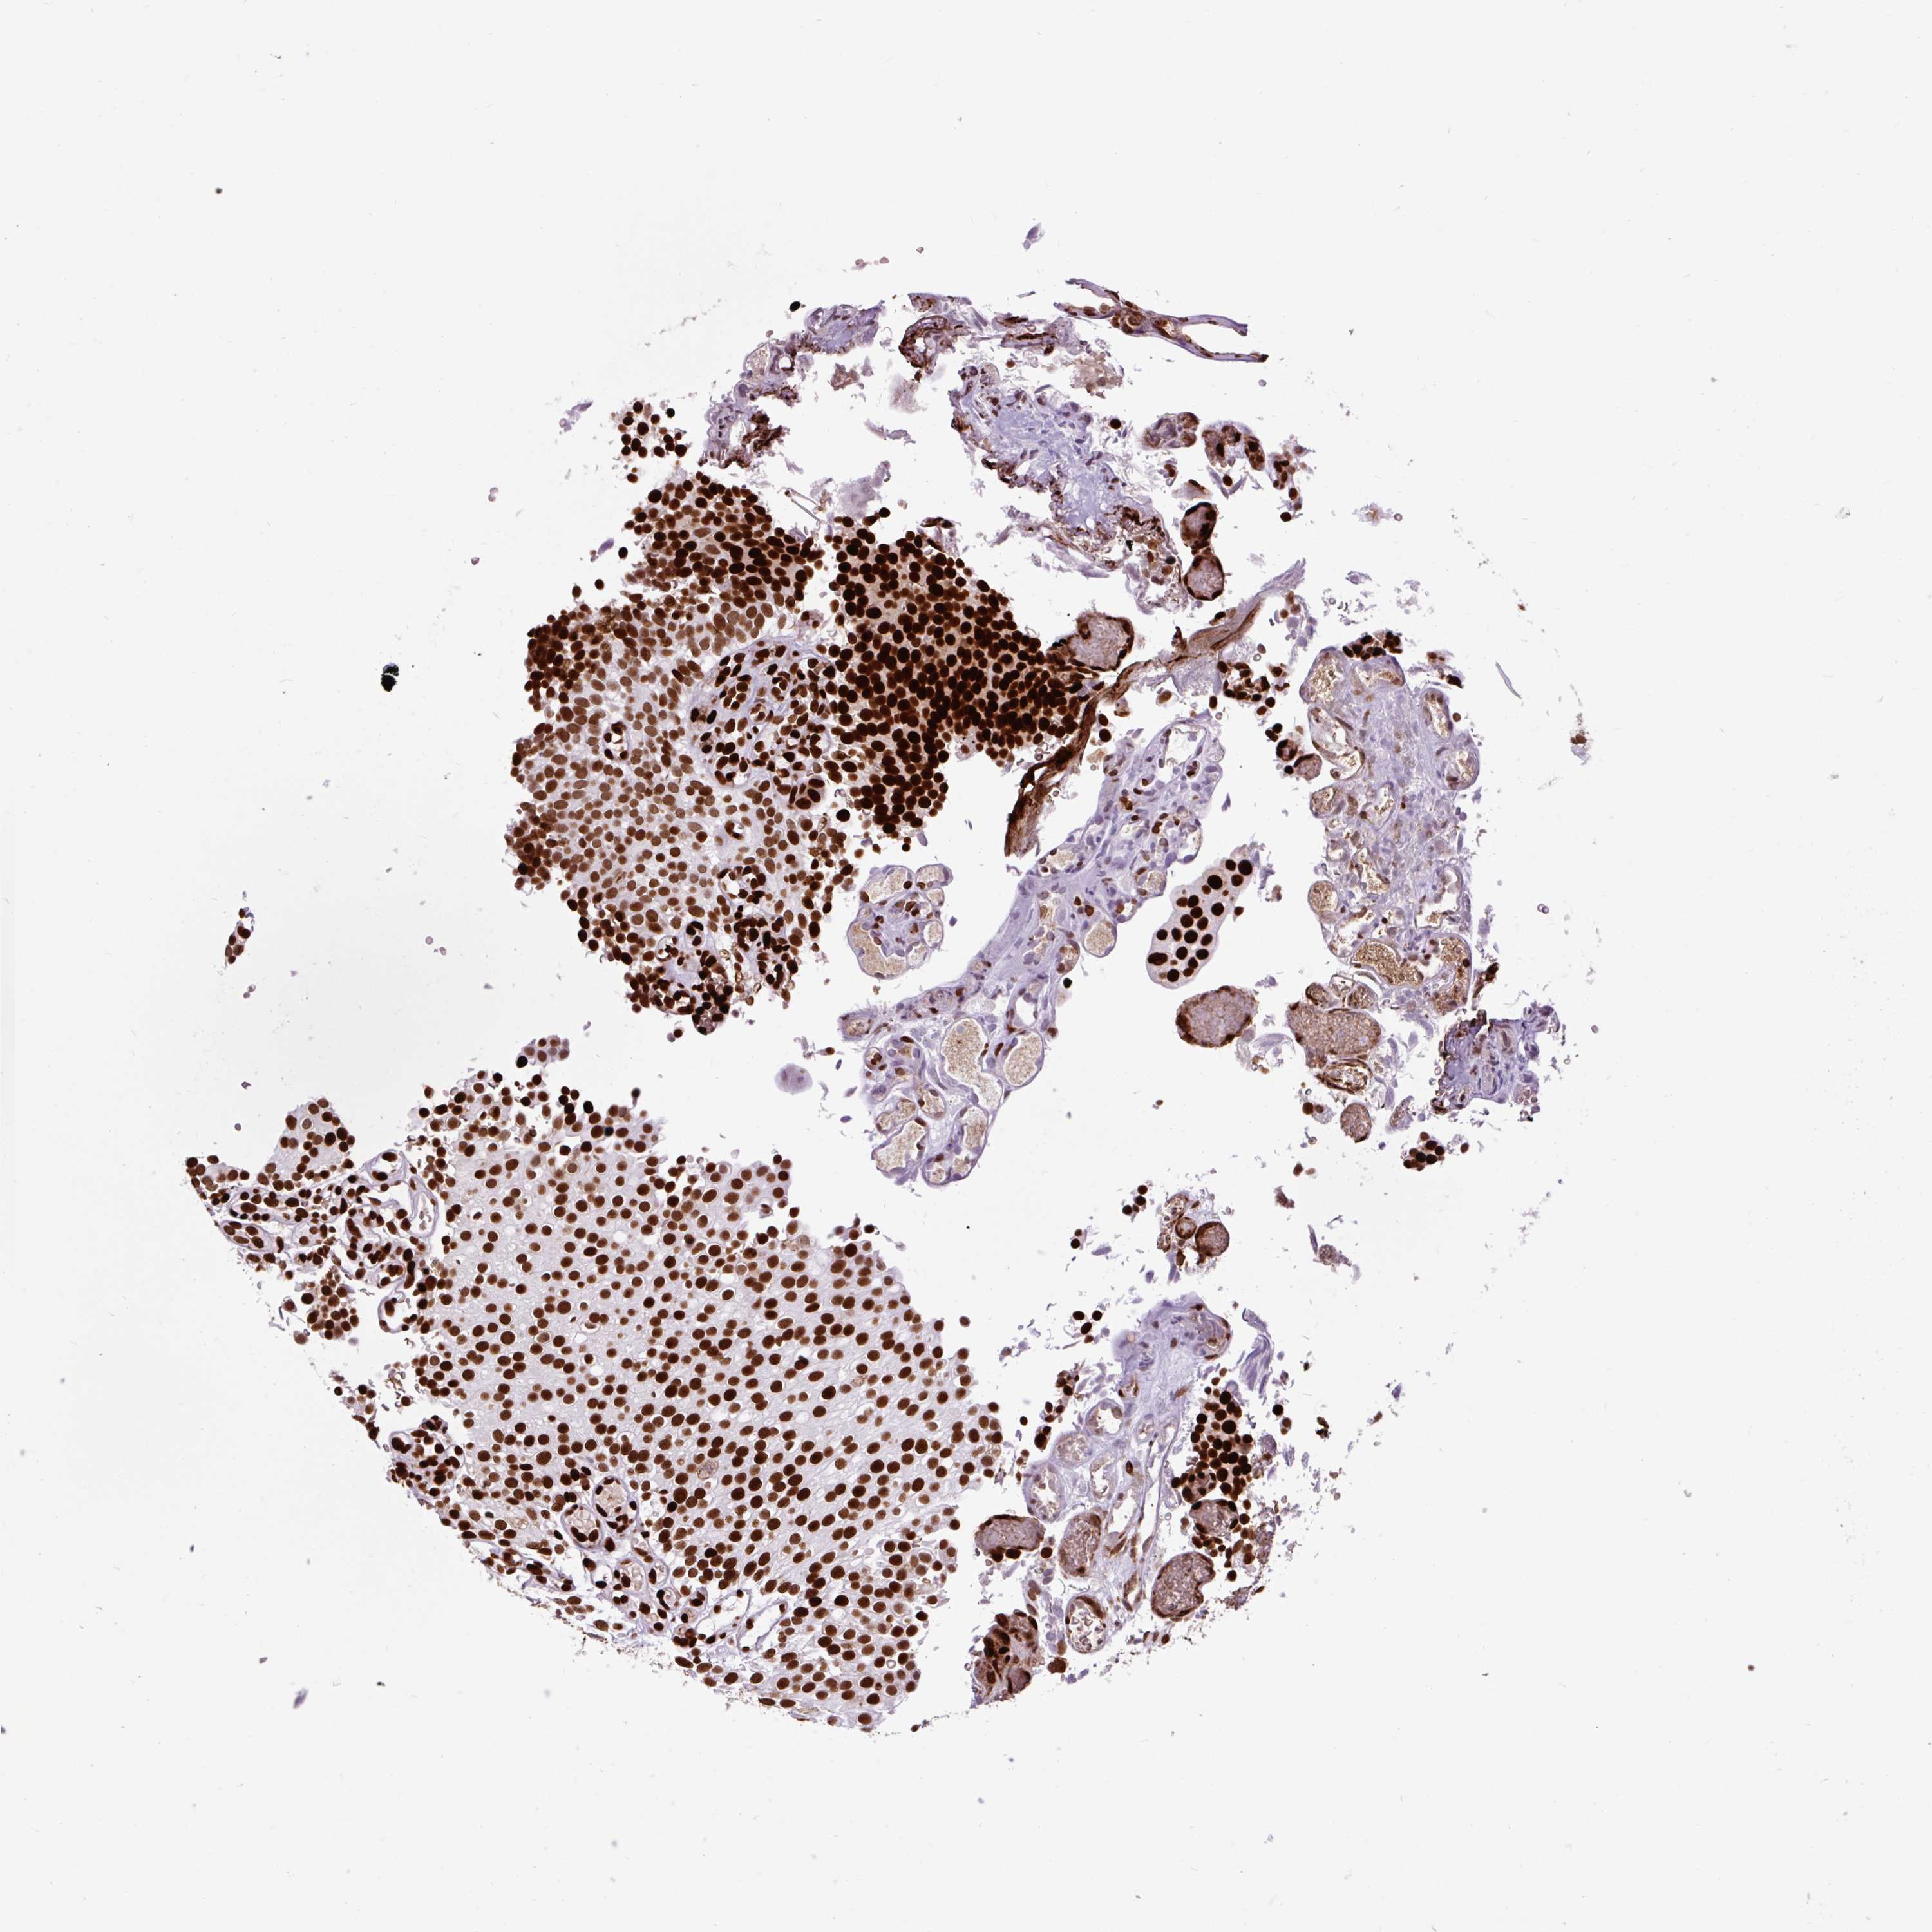

UROTHELIAL CANCER - Protein expressioni

A mouse-over function shows sample information and annotation data. Click on an image to view it in a full screen mode. Samples can be filtered based on level of antibody staining by selecting one or several of the following categories: high, medium, low and not detected. The assay and annotation is described here.

Note that samples used for immunohistochemistry by the Human Protein Atlas do not correspond to samples in the TCGA dataset.

Antibody stainingi

Antibody staining in the annotated cell types in the current human tissue is reported as not detected, low, medium, or high, based on conventional immunohistochemistry profiling in selected tissues. This score is based on the combination of the staining intensity and fraction of stained cells.

Each image is clickable and will lead to virtual microscopy that enables deeper exploration of all samples and also displays staining intensity scores, fraction scores and subcellular localization as well as patient and tissue information for each sample.

Antibody HPA008784

Antibody CAB033036

Antibody CAB058691

Staining

High

Medium

Low

Not detected

Intensity

Strong

Moderate

Weak

Negative

Quantity

>75%

75%-25%

<25%

None

Location

Nuclear

Cytoplasmic/membranous

Cytoplasmic/membranous,nuclear

Urothelial carcinoma, Low grade

Urothelial carcinoma, High grade

Urothelial carcinoma, NOS